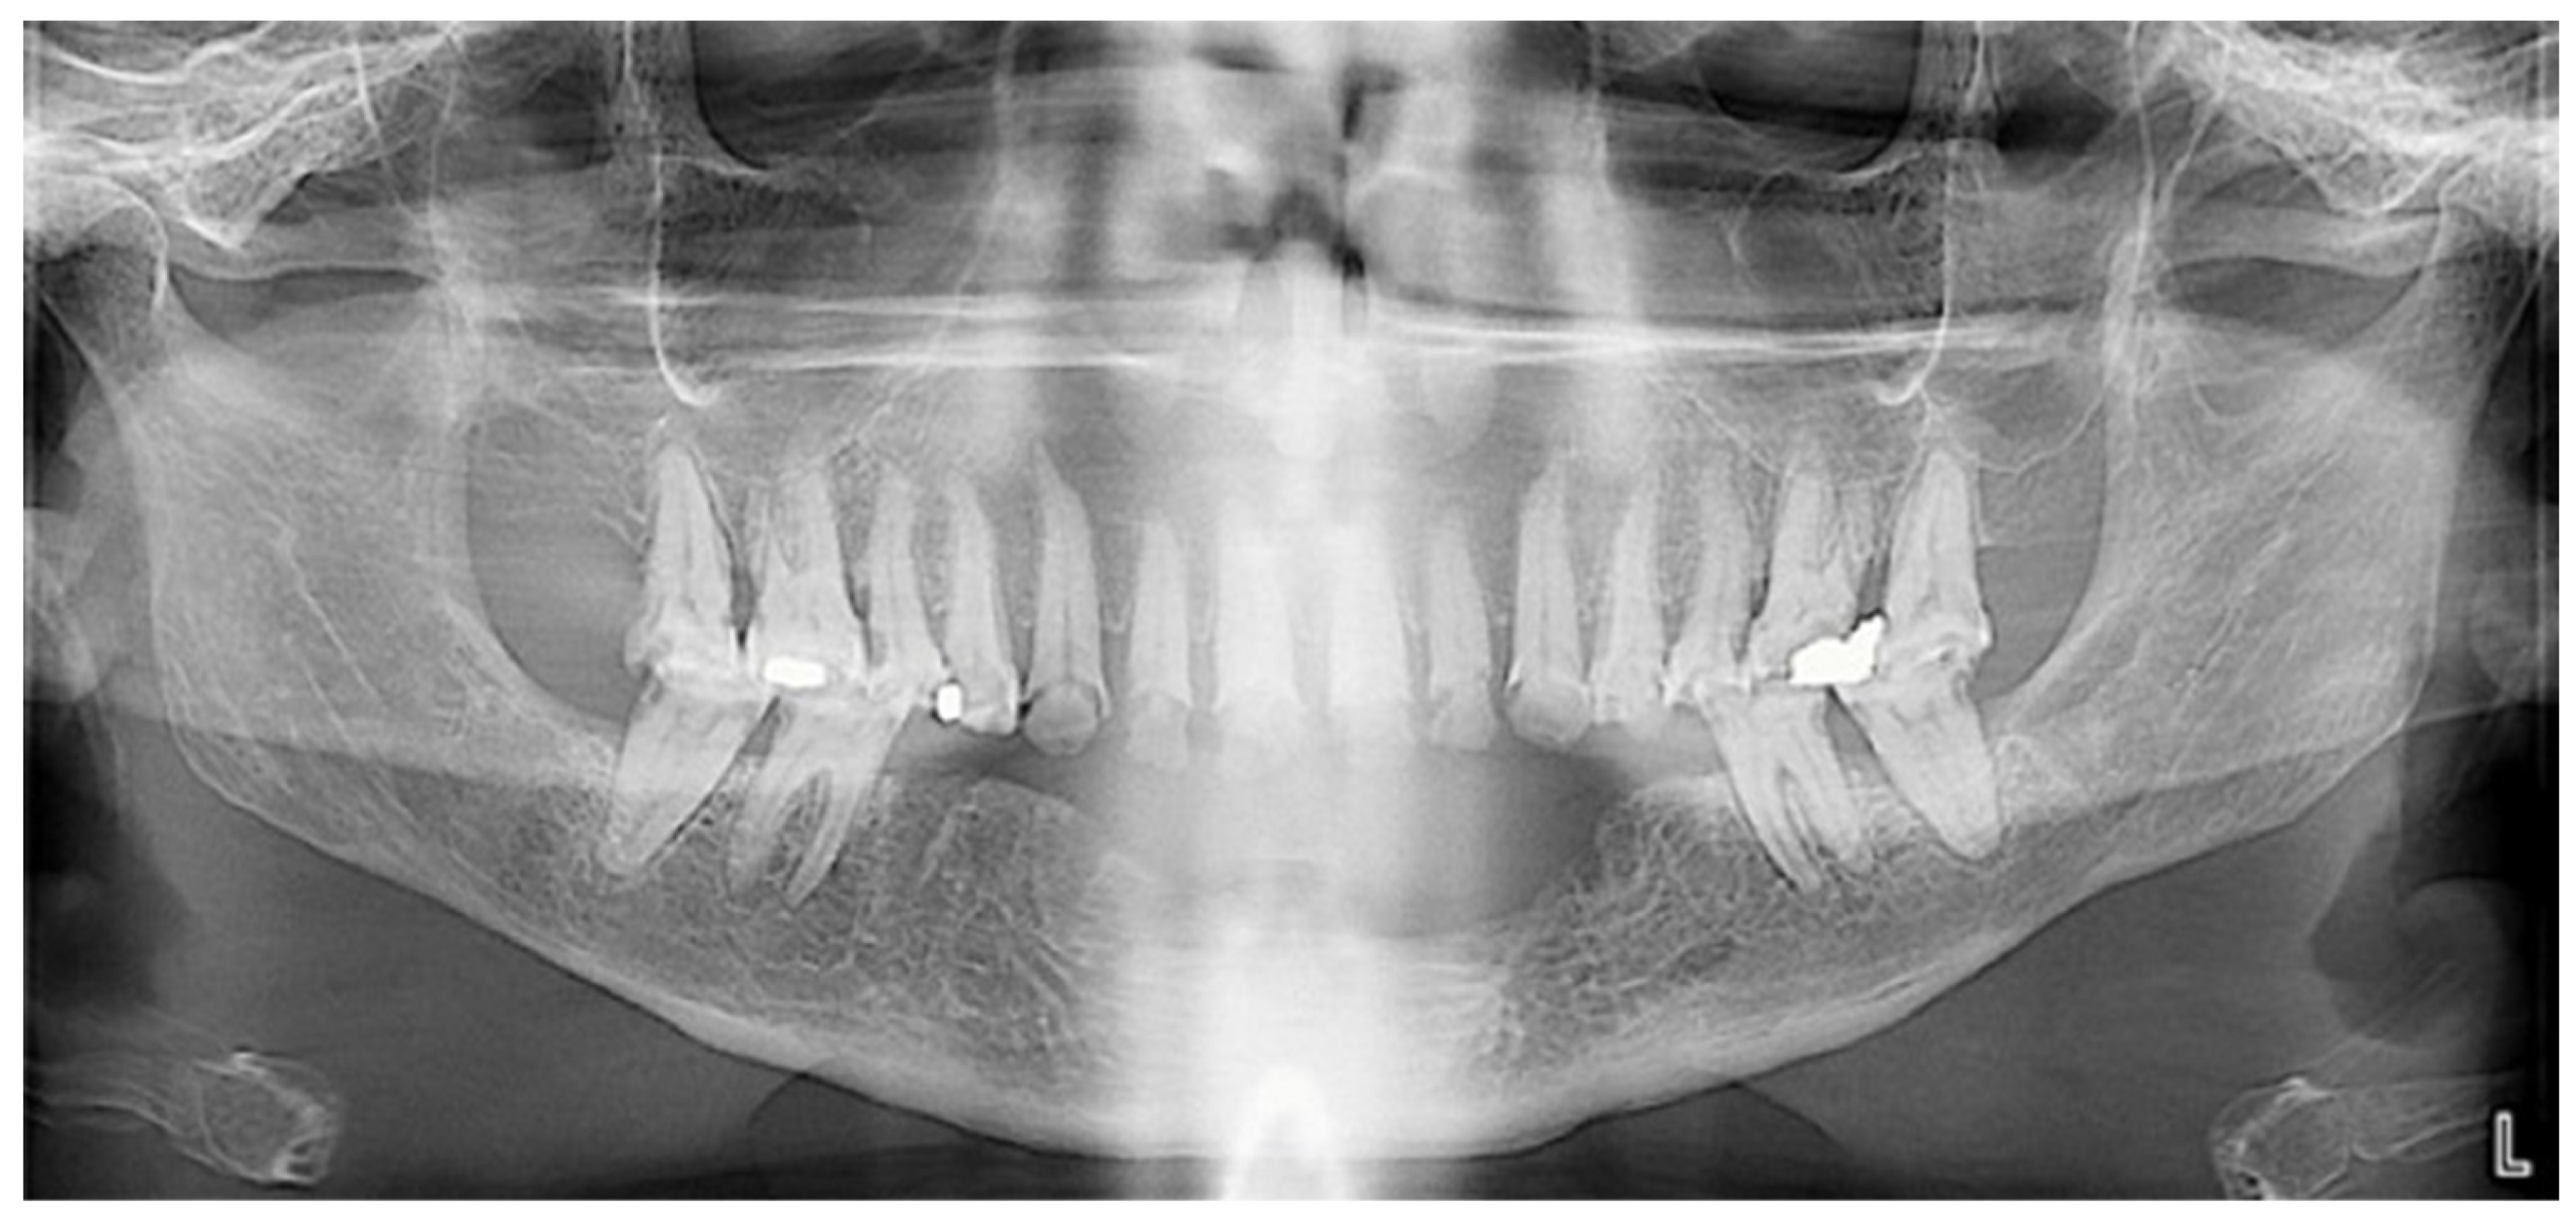

Extraoral examination revealed an unaesthetic smile, radiation-induced caries (Figure 1A), and mandibular retrognathia following carcinoma resection. The occlusal vertical dimension (OVD) was slightly reduced. Intraoral examination showed extensive decay in the remaining teeth (17 to 27, 36, 37, 46, and 47), with most being painful to percussion and highly sensitive to cold. Compromised restorations were noted in teeth 17, 16, 14, and 26 (Figure 2). The gingiva was inflamed and extremely sensitive, and the alveolar ridge in the mandibular incisal region was severely resorbed. Radiographic examination confirmed that 26 and 17 were non-restorable due to advanced root decay and periodontal disease (Figure 3).

Figure 3.

Panoramic radiograph before treatment.